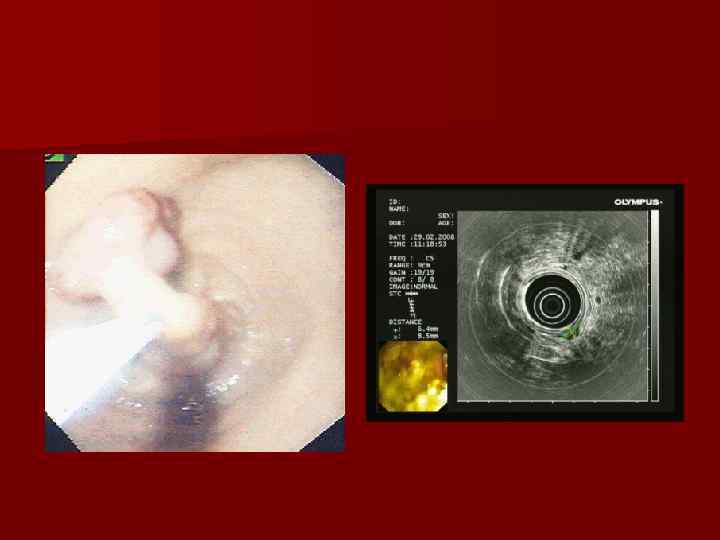

2. Инструментальная диагностика рака желудка n а. Эндоскопическое исследование (фиброгастродуоденоскопия) Благодаря эндоскопическим методам исследования можно визуально выявить опухоль. При этом можно оценить ее размеры, характер роста, наличие кровоточивости, изъязвлений, ригидности слизистой оболочки желудка. Немаловажно и то, что во время фиброгастроскопии можно взять участок опухоли для морфологического исследования (биопсия). Но, к сожалению, информативность однократной биопсии чаще всего не превышает 50% и для установления точного морфологического диагноза необходимо выполнение нескольких биопсий.

Гастроскопия: рак кардиального отдела желудка с переходом на пищевод.